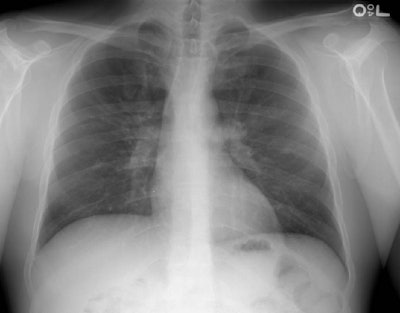

Subtle Cystic Fibrosis:

The 26 year old patient with cystic fibrosis shown in the chest radiograph below demonstrates only subtle findings of the disease. Peribronchial cuffing is identified about the right central bronchi and mild bronchial thickening is seen in the right upper lobe. Some branching shadows are also note in the right upper lobe. Less severe changes are noted in the left upper lobe.